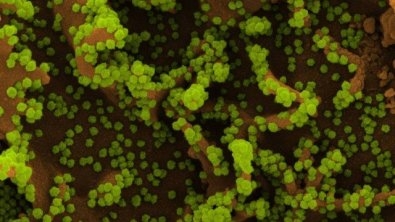

Nova variante do coronavírus já tem nome: 'Nu'

Apesar de a OMS ainda não ter anunciado oficialmente o nome da nova variante, especialistas internacionais já apontam Nu como o provável nome da nova cepa, por conta da lógica do alfabeto grego.